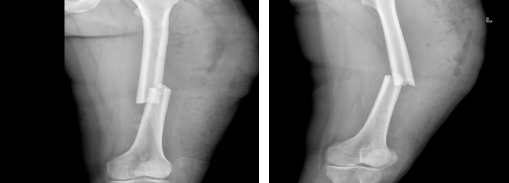

图7、8术后复查DR 图9术后换药治疗

此例微创下切开复位手术在省医院姚豹医生助力下成功开展,同时标志州人民医院骨科微创技术再上新阶,为今后该类疾患治愈积累经验。